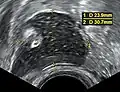

Dermoid cyst in vaginal ultrasonography -